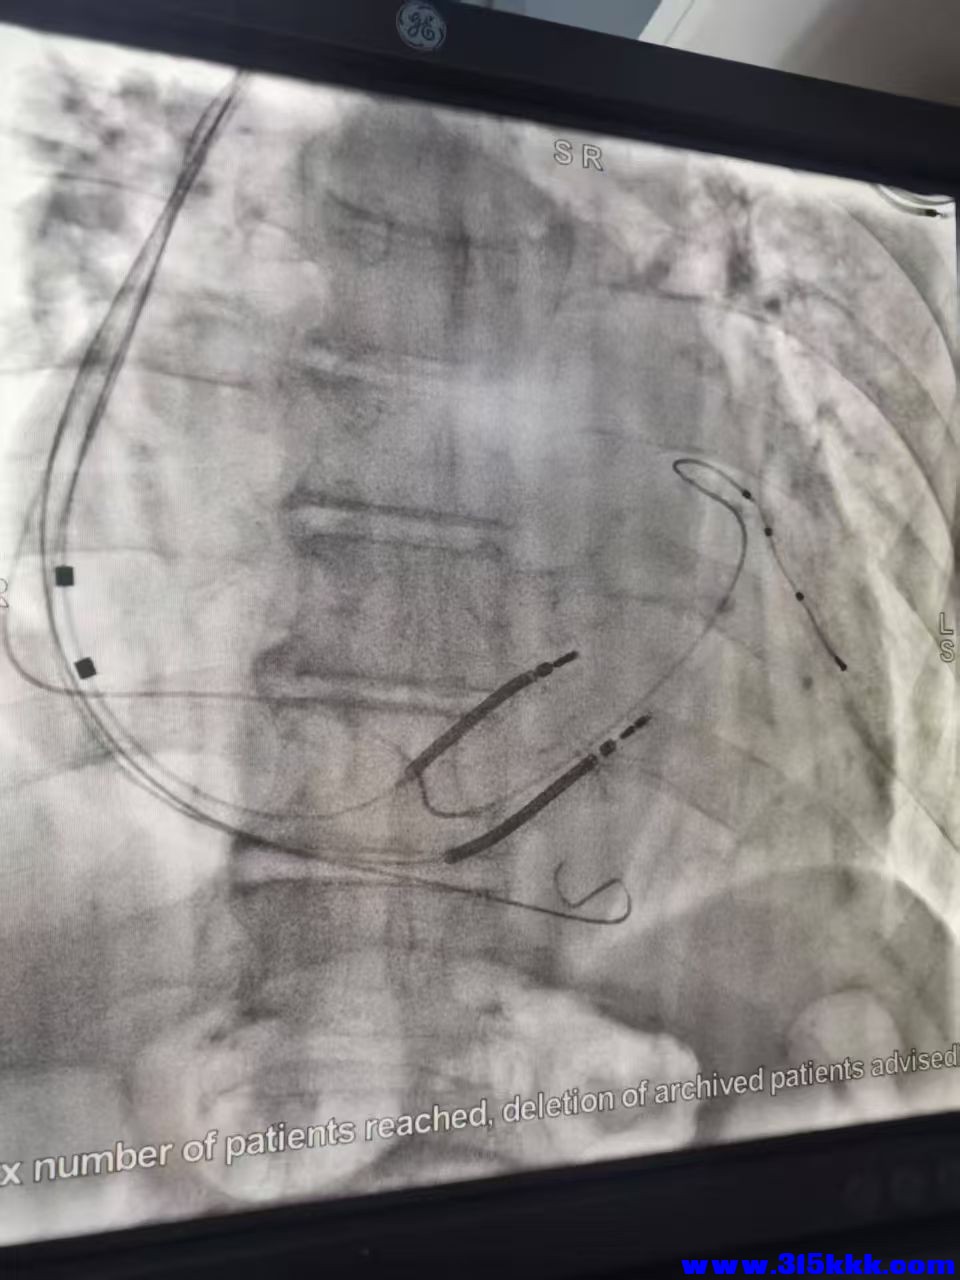

手术室拍摄心脏介入消融术过程

心脏介入消融术通过将‌特制导管‌经血管(如股静脉或股动脉)送至心脏特定部位,利用‌射频能量(热消融)‌或‌冷冻能量(冷消融)‌破坏导致心律异常的病灶组织。异常心肌细胞被破坏后,心脏电活动恢复正常,心律失常得到控制。

手术室因为特殊的清洁要求,空调系统跟医院大楼的大空调系统不是同一个的,自己有一套小型空调机组专门为手术室供暖气(冷气),空气循环净化要求高,而且手术室内必须是正压的,也就是室内空气压力必需略大于外界空气压力,这样在开关门的时候,正压能有效阻止外部未净化空气或污染物进入手术区域,保障室内空气洁净度。这几天本地降温厉害,手术室空调暖气不足,临时搞了5~6台电暖气凑合,昨天我以前的同事去维修,因为问题有点复杂就让我也一起过去了,进手术室就让我们换了鞋子,每人给了一个口罩和一个一次性帽子(跟厨司那个帽子差不多),其它衣服什么的也都没要求有换,我们搞我们的机器,2台手术在同时进行着,和我们只隔了一道帘子,井水不犯河水。